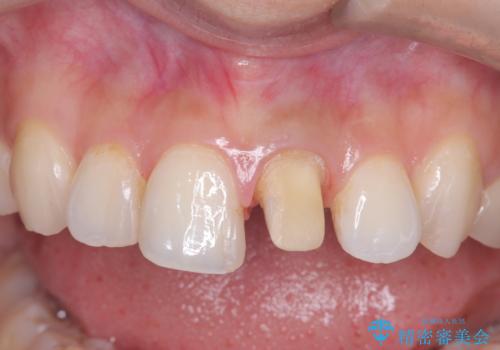

- 「前歯の色が気になる」を主訴に来院された患者様です。

前歯にプラスチックの材料が入っており、形と色が悪くなっていました。

失活歯だったため全体的に歯の色が暗くなっていました。

右上1もCRが入っており治療を勧めましたが、希望されず左上1のみ行いました。